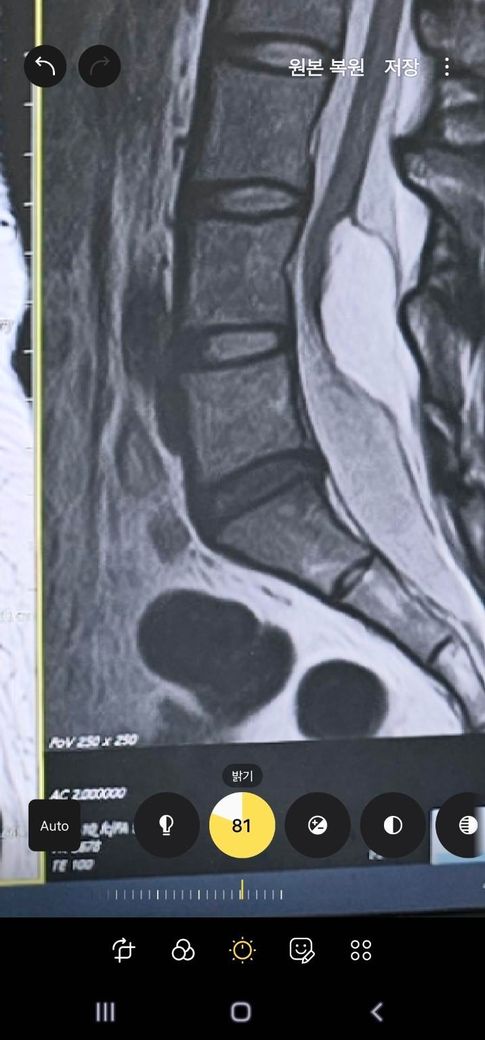

이런 상황이고 미세돌출??같아보여요 의사샘들은 다 안 심하다고 신경 안 누른다고 했는데.. 저는 원체 예민해서 허리아프고 방사통도 있거든요ㅠㅠ아무튼 10월에 미국 가서 디즈니월드랑 유니버셜 가서 놀이기구 타고 싶은데... 자이로드롭 이런건 안탈거구요 롤러코스터는 탈거예요 티익스프레스만큼 격한건 없는거같은데 어쨌든 롤코니까 걱정돼서요ㅠㅠ 10월까지 재활 피티로 허리 근육 코어 근육 등 강화하고, 허리 보호대 차서 놀이기구 타면 좀 보호할 수 있을까요?ㅠㅠㅠ3

• 1번 째 사진